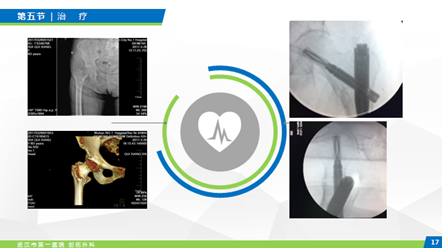

五、治疗